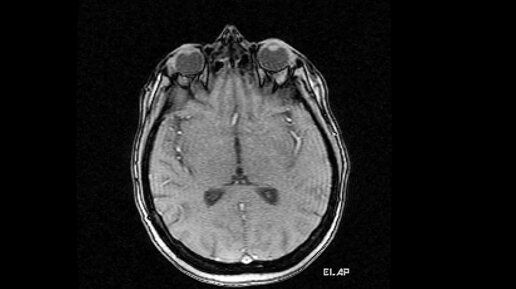

Что покажет МРТ головного мозга и шейного отдела позвоночника (видео)